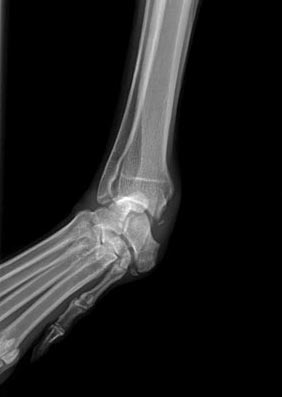

Kurz vor Weihnachten 2016 hat Carla sich beim Toben einen Bruch und kompletten Bänderriss im Karpalgelenk zugezogen.

Nachdem das Gelenk mit einer Platte und 11 Schrauben versteift wurde, mussten wir sie monatelang schonen.